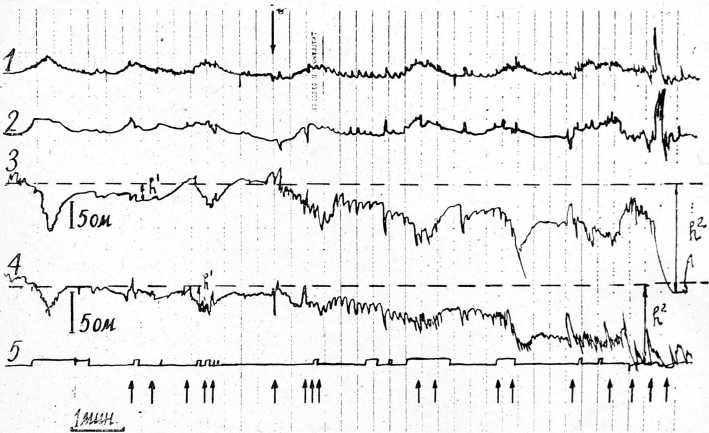

Рис. 1. Сократительная деятельность и кровенаполнение матки, двигательные реакции плода при обезболивании родов метокеифлураном у роженицы Б., 25 лет. Открытие шейки матки — 5 см. Околоплодные воды целы.

Обозначения: 1 и 2 — механограммы тела матки и нижнего маточного сегмента соответственно; 3 и 4 — электроплетизмограммы тела и нижнего маточного сегмента соответственно; 5 — отметка субъективных ощущений роженицей начала и конца схваток; 6 — отметка времени — 20 с. К—калибровка эЛектроплетйзмографов. Стрелкой над механограммой тела^ матки обозначено .начало обезболивания метокеифлураном; стрелками под электроплетизмограммой нижнего сегмента — шевеления плода.

На механограммах (МГ) и особенно электроплетизмограммах (ЭПГ) матки через 2—3 мин . от начала аутоанальгезии определялось увеличение длительности сокращений тела матки и тенденция к снижению активности нижнего маточного сегмента. Так, если без применения обезболивания длительность сокращений матки при открытии шейки матки на 6—10 см составляет 89,3 + 3,7 и 103 + 4,2 с по данным МГ и ЭПГ соответственно, а амплитуда сокращений матки равна по данным МГ 24 + 1,19 мм и по данным ЭПГ — 9,78 + 0,63 ом, то у рожениц с применением аутоанальгезии продолжительность схваток достоверно больше, чем в контрольной группе, и составляет 98,8 + 3,8 с по данным МГ и 116,4+ 4,23 с по данным ЭПГ (Р<0,05). Амплитуда сокращений матки существенно не отличается от этих показателей контрольной группы и по данным МГ равняется 25 + 1,21 мм и 11,1 + 0,7 ом по данным ЭПГ (Р>>0,05).

При обезболивании родов метокеифлураном у рожениц со своевременным излити- ем -околоплодных вод по данным механографии существенных изменений тонуса матки. не происходит, в то же время электроплетизмографически всегда выявляется увеличение ме.ждуэлектродного импеданса матки. Возможно это связано с сосудистыми реакциями матки. При анализе двигательной активности плода мы всегда обнаруживали существенное увеличение числа обобщенных двигательных реакций. Шевеление плода вызывает появление на электроплетизмограмме матки осцилляций с амплитудой 0,5 — 2 ом и длительностью 2—5 с.

У рожениц без обезболивания частота шевелений плода в первом периоде родов за 10 мин доставляет 2,5 + 0,23, а у рожениц с обезболиванием метокеифлураном частота обобщенных двигательных реакций повышается за 10 мин до 6,3 + 0,51 (Р<С,0,01). При этом выслушивание сердцебиения плода не выявило значительных изменении в состоянии плода.